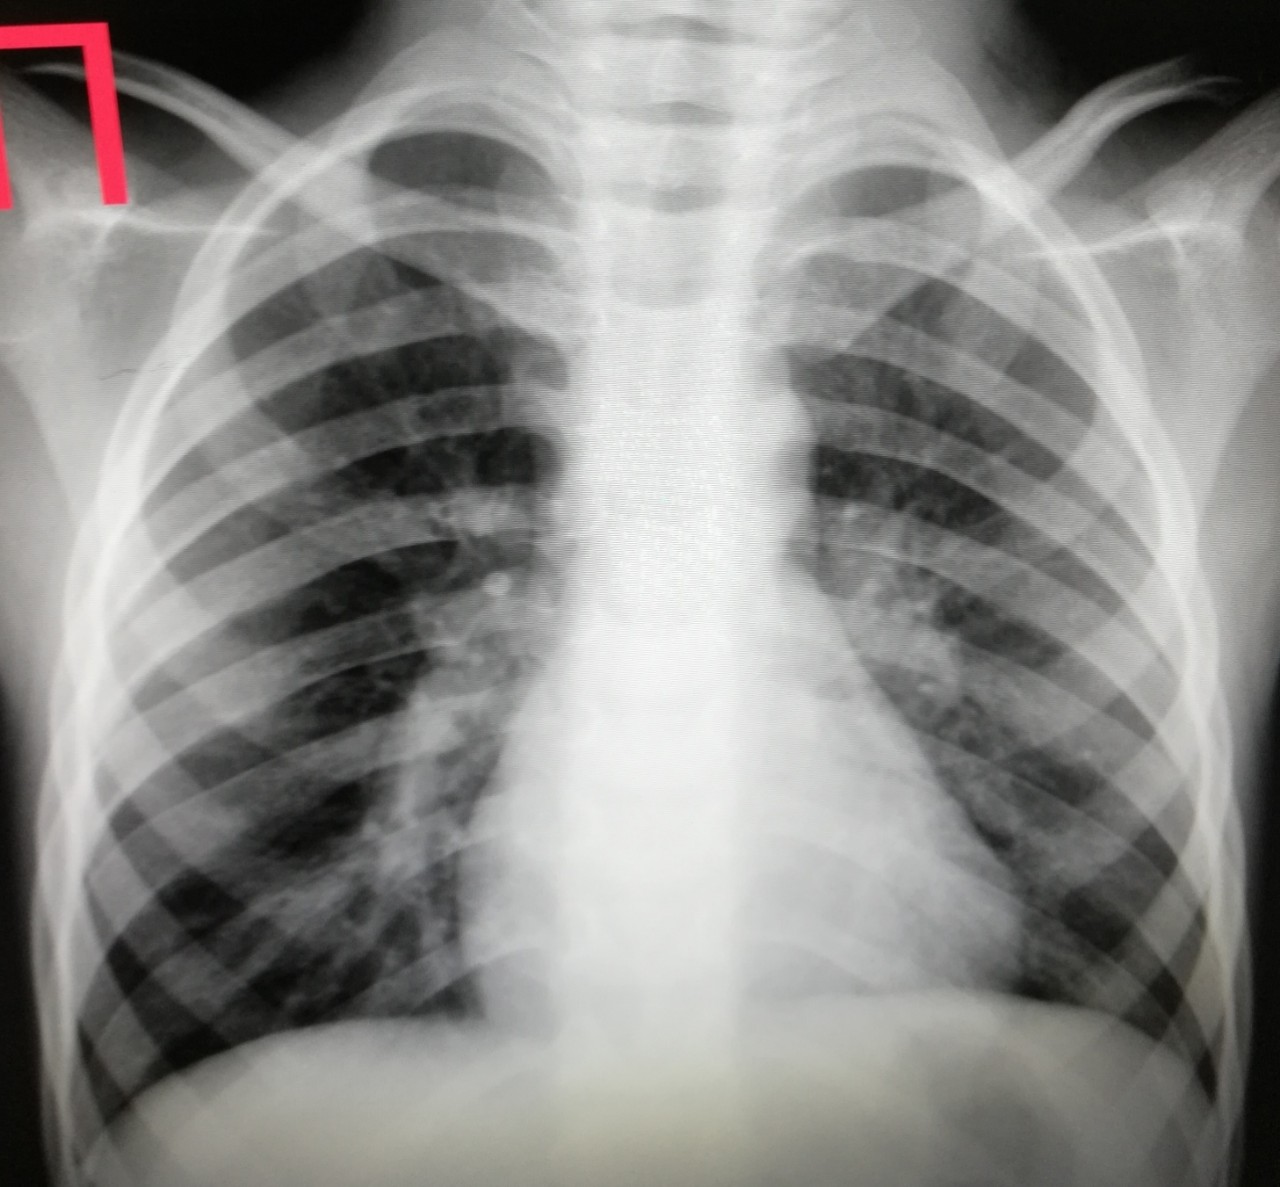

Поражение легких является одним из основных симптомов коронавируса (COVID-19). В данной статье представлены фото рентгеновских снимков, которые позволяют визуально оценить состояние легких при этом заболевании.

Рентген легких ковид 19

На фотографиях рентгеновских снимков видно, как вирус воздействует на легочную ткань. Характерные признаки поражения легких включают пятна, инфильтраты и наличие жидкости внутри легочных альвеол.

Фото рентгеновских снимков помогают врачам и специалистам визуально определить степень поражения легких и принять соответствующие меры лечения и поддержки пациента.